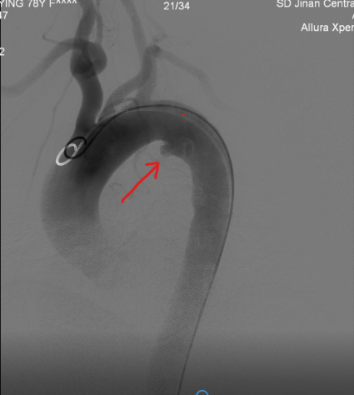

*术中主动脉弓部造影可见小弯侧箭头处明显穿透性溃疡